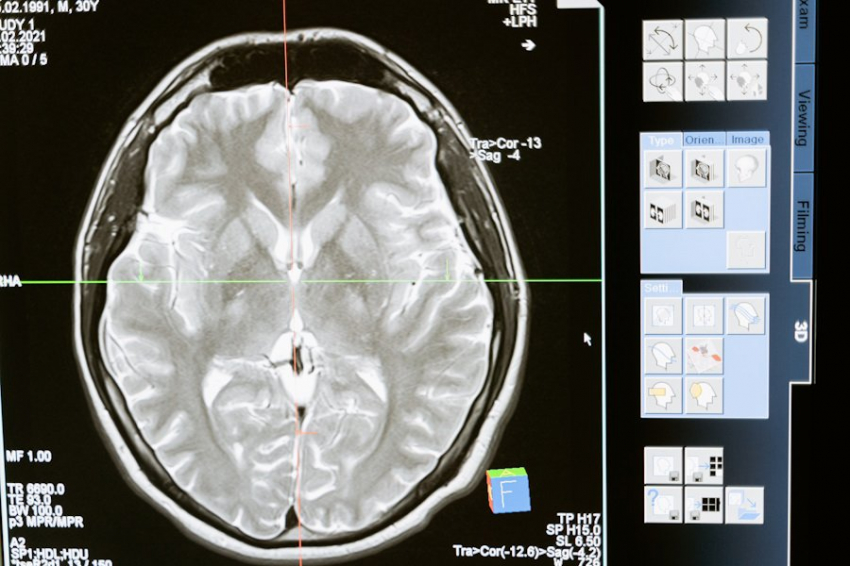

Исследователи из Университета Юты создали уникальное ультразвуковое устройство, которое устанавливается на голове и воздействует на глубокие структуры мозга. Устройство под названием «Диадема» уже прошло два успешных испытания на людях, продемонстрировав свою эффективность в лечении хронической боли и депрессии, сообщает PAIN.